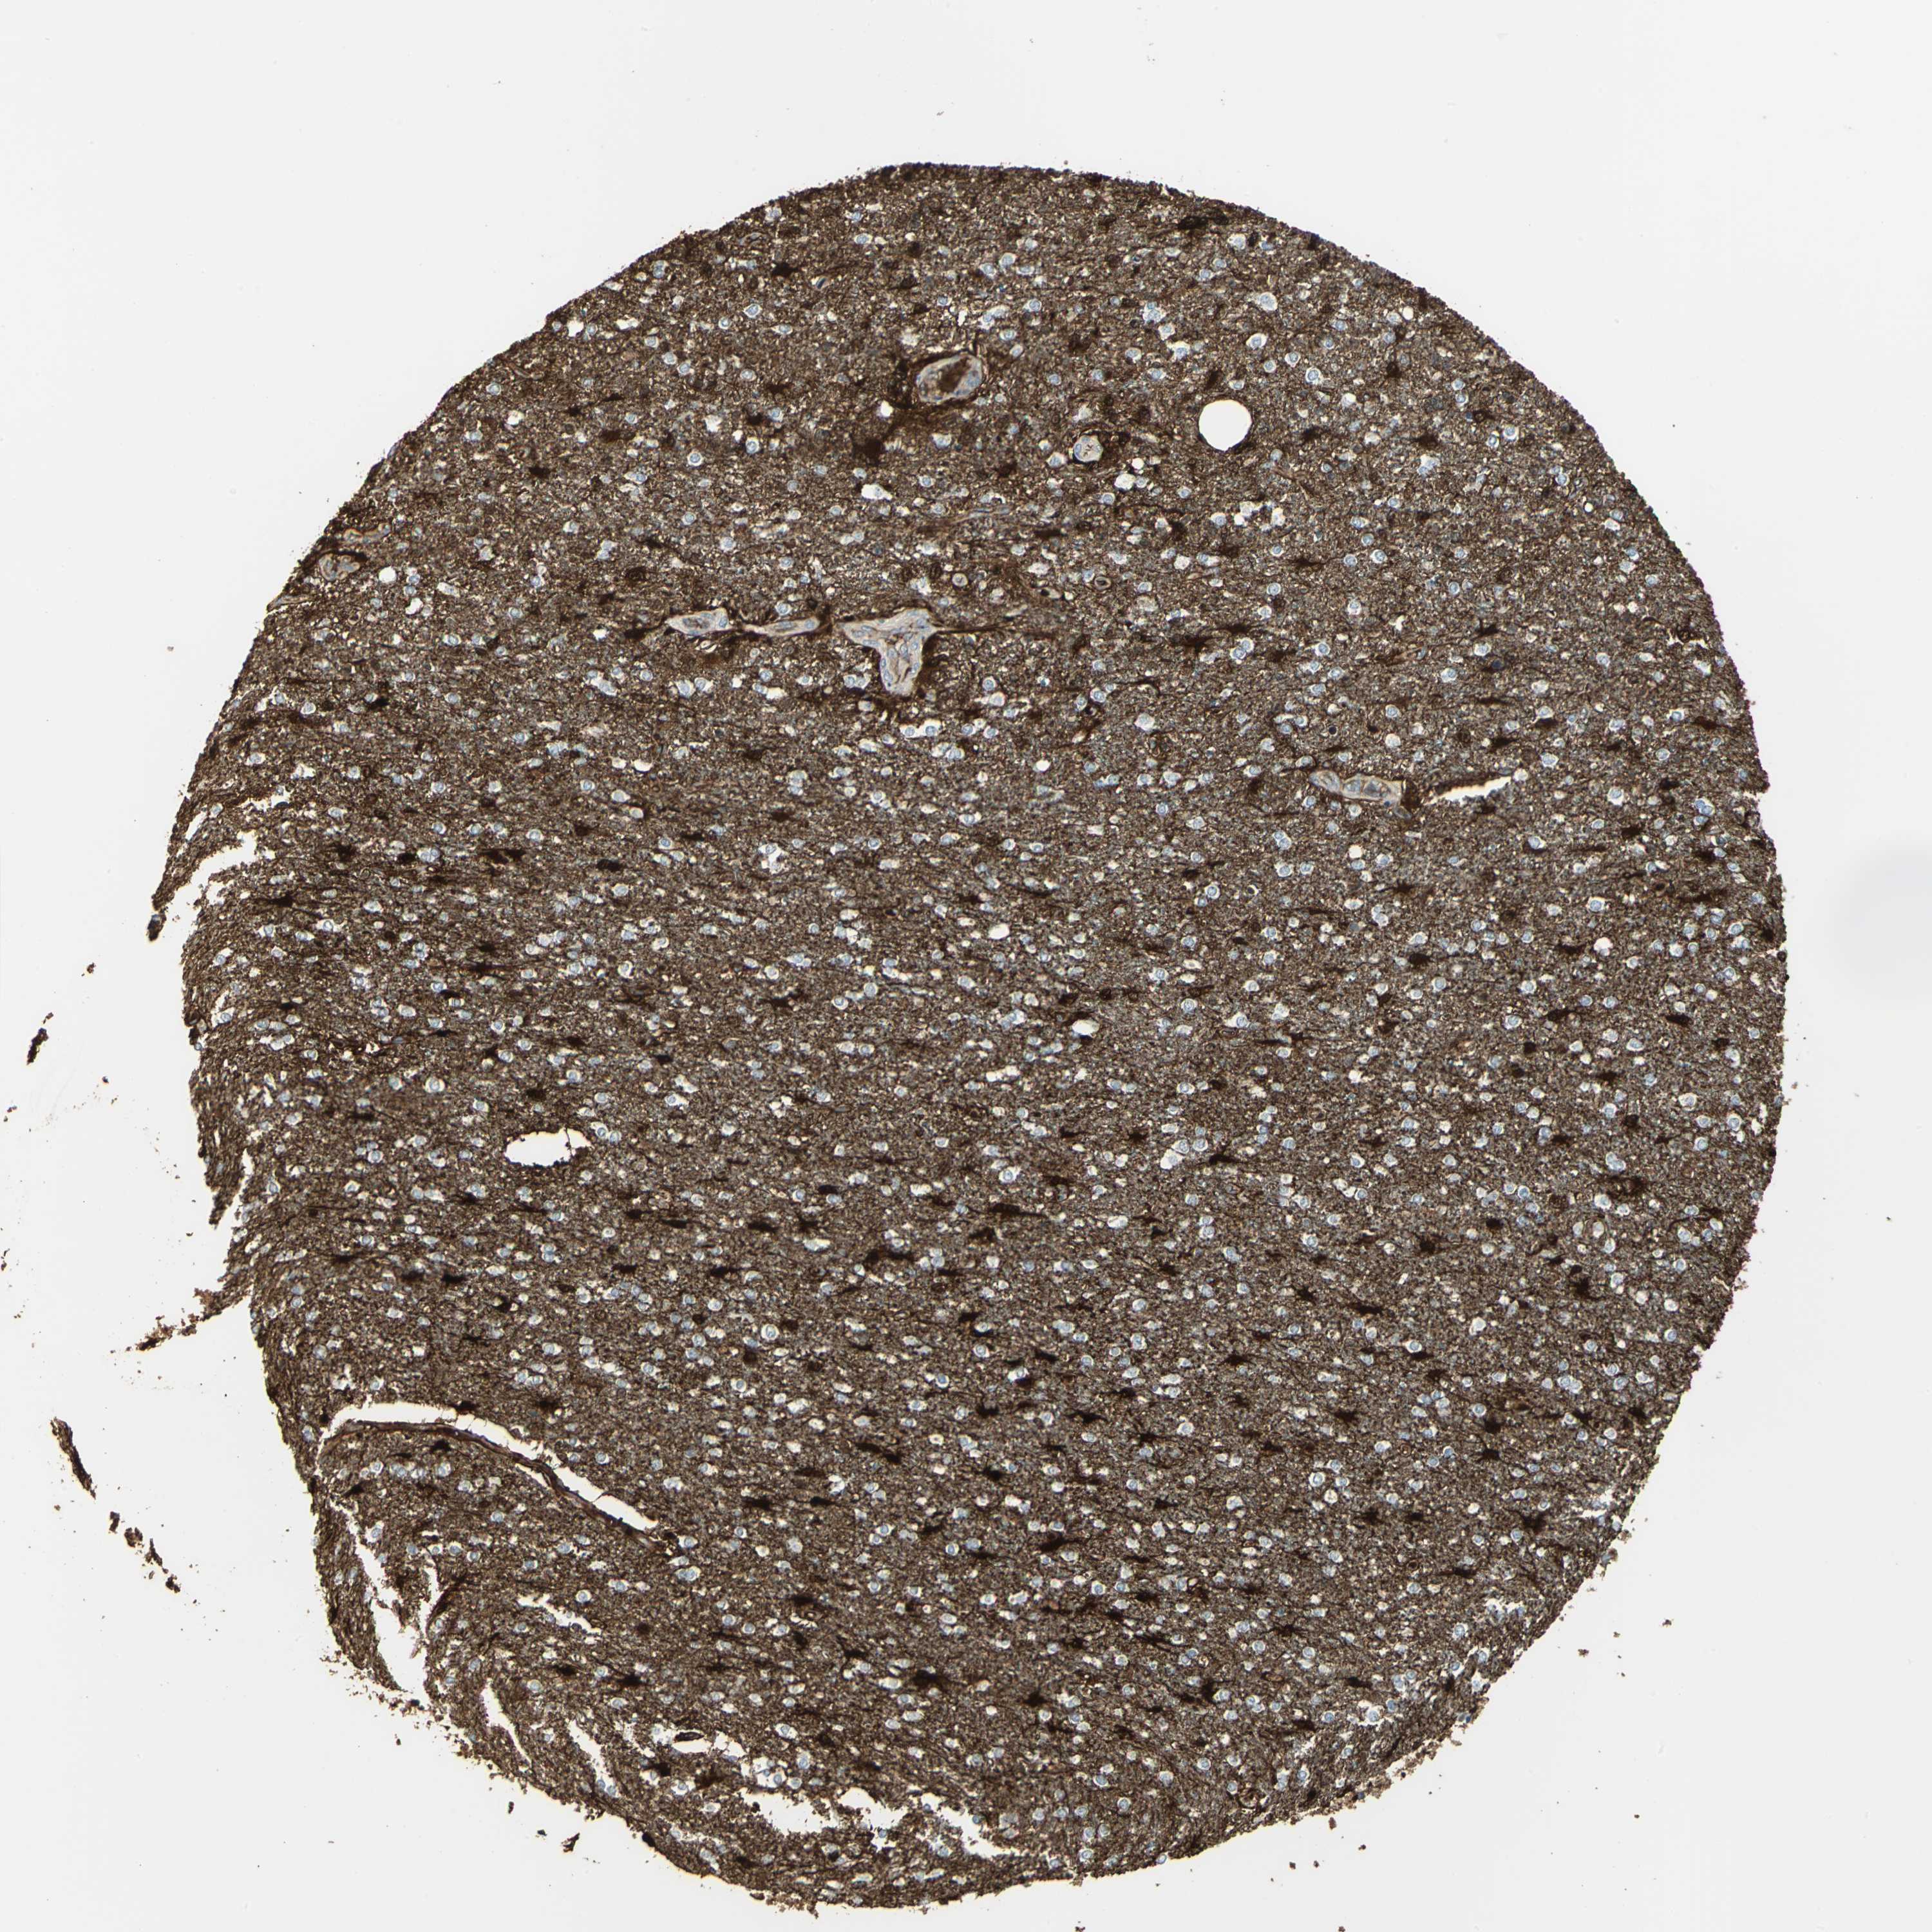

GLIOMA - Protein expressioni

A mouse-over function shows sample information and annotation data. Click on an image to view it in a full screen mode. Samples can be filtered based on level of antibody staining by selecting one or several of the following categories: high, medium, low and not detected. The assay and annotation is described here.

Note that samples used for immunohistochemistry by the Human Protein Atlas do not correspond to samples in the TCGA dataset.

Antibody stainingi

Antibody staining in the annotated cell types in the current human tissue is reported as not detected, low, medium, or high, based on conventional immunohistochemistry profiling in selected tissues. This score is based on the combination of the staining intensity and fraction of stained cells.

Each image is clickable and will lead to virtual microscopy that enables deeper exploration of all samples and also displays staining intensity scores, fraction scores and subcellular localization as well as patient and tissue information for each sample.

Antibody HPA006308

Antibody HPA071064

Glioma, malignant, Low grade

Glioma, malignant, High grade